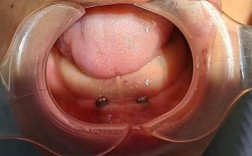

是否需要附加手术:复杂情况延长治疗周期

部分患者在种植牙时可能需要同时进行其他手术,这些附加操作会延长牙冠佩戴时间:

- 上颌窦提升术:当上颌后牙区牙槽骨高度不足时,需将上颌窦底黏膜向上提升,植入骨粉,根据手术方式(上颌窦内提升术或外提升术),愈合时间需4-6个月;